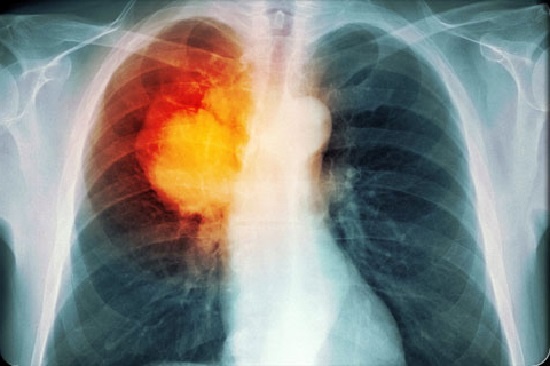

![]() |

| Khói thuốc lá cũng có tác động tiêu cực tới phổi và gây ra ung thư phổi. Ảnh: Medicinenet. |